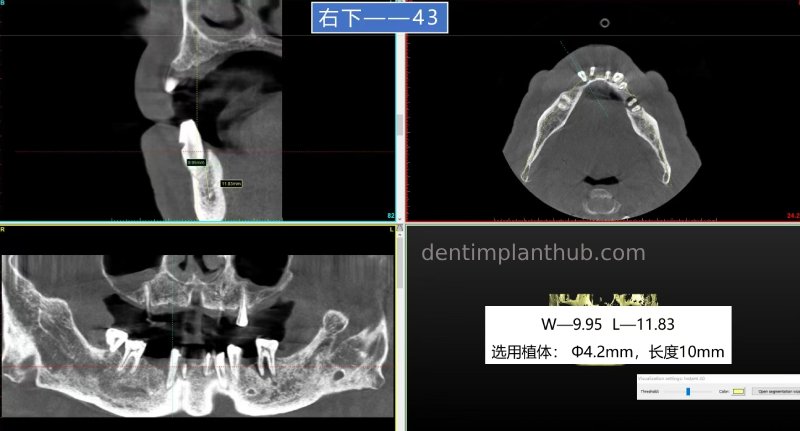

43, ready to be extracted, ready to be implanted. Follow-up restoration and 45 together with continuous crowns;

43, ready-to-use implant, implant model 4210, with 0.25g of bone meal and one 1.5*2 oral biofilm;